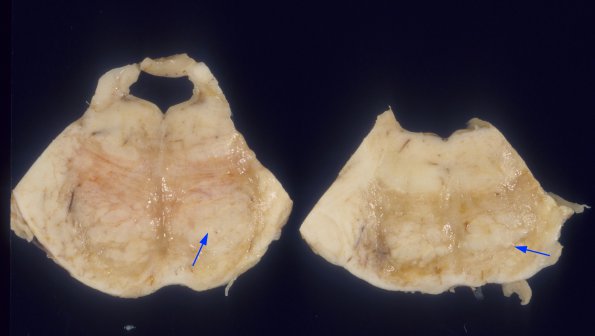

This case was characterized by extensive and unusual involvement of the brainstem, particularly sparing the descending corticospinal tracts (arrows).